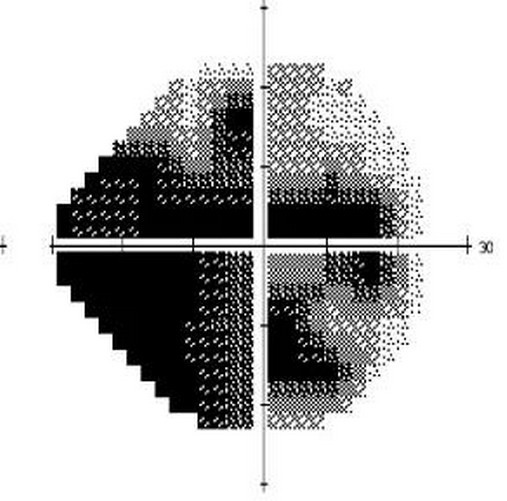

圖 | 患者右眼視野

經(jīng)診斷,小伙子患有雙眼開角型青光眼(左眼無光感,右眼晚期青光眼)。雖然平時沒有察覺,但青光眼已悄然“偷走”他左眼全部的視力,右眼視野也僅剩26%,所以他騎車時無法看見前方的泥坑。深感惋惜的同時,正確認識青光眼就顯得更加重要。

視野是指人的頭部和眼球固定不動的情況下,眼睛觀看正前方物體時所能看得見的空間范圍(上述視野檢查圖中黑色部分表示視野缺損看不見)。